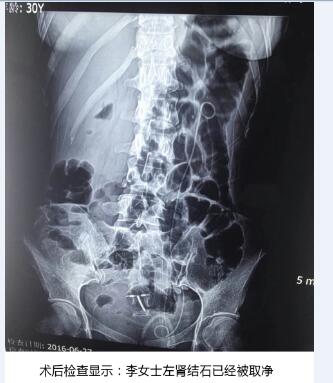

在天津百信医院结石病诊疗首席医生丁德刚主任的带领下,经过医生组周密讨论和精心会诊,一致认为该手术对医生技术和设备要求很高。如果对肾脏结构把握不好,容易造成术中出血量多,肾脏损伤大。终决定为李女士实施PCN+EMS术式(经皮肾镜联合超声碎石取石术)。从天津百信医院结石病诊疗首席医生丁德刚主任口中得知,该术大的优势——利用超声碎石清石系统将结石击碎吸出,再利用等渗盐水冲洗,冲出微小结石碎块,术中患者出血很少,手术非常。术后检查结果显示,取石率达到100%。

经过1个半小时手术,将李女士体内“心形”结石清除干净,手术非常顺利。